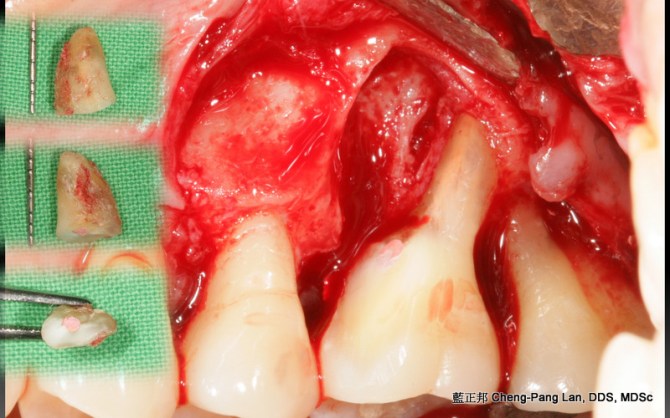

Root Amputation – Case A

This entry was posted in Treatment of Furcation-Involved Teeth and tagged Furcation, Root Amputation. Bookmark the permalink.